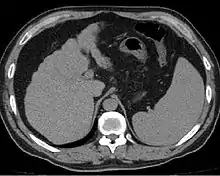

Other scans include CT of the abdomen and MRI.[35] A CT scan is non-invasive and may be helpful in the diagnosis.[35] Compared to the ultrasound, CT scans tend to be more expensive. MRI provides excellent evaluation; however, is a high expense.[35]